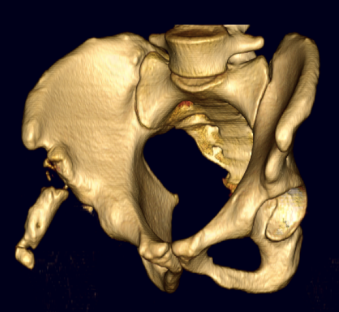

ASIS CT 1ASIS CT 2ASIS CT 3

AIIS avulsion 1AIIS avulsion 2AIIS avulsion 3